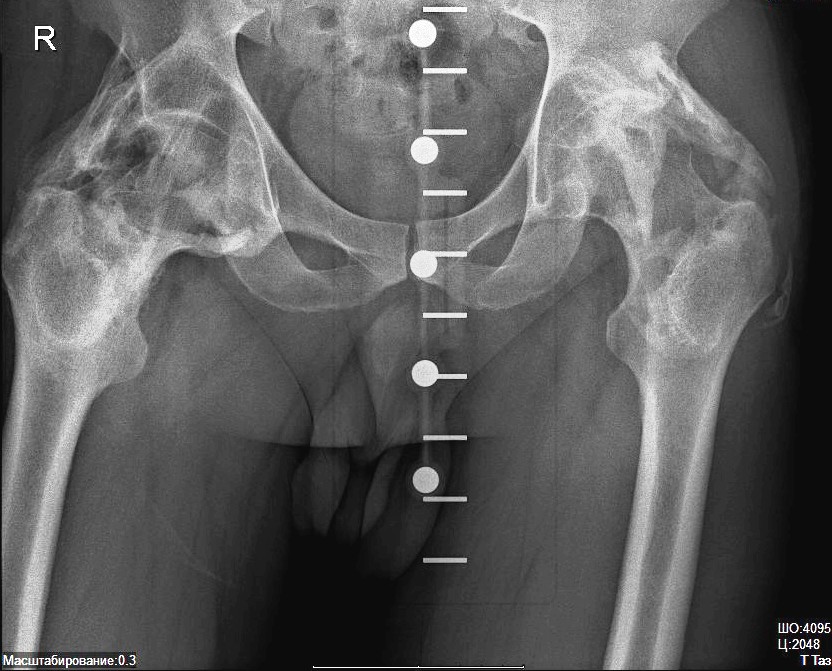

Рентгеновские снимки анкилоза суставов: Как это выглядит